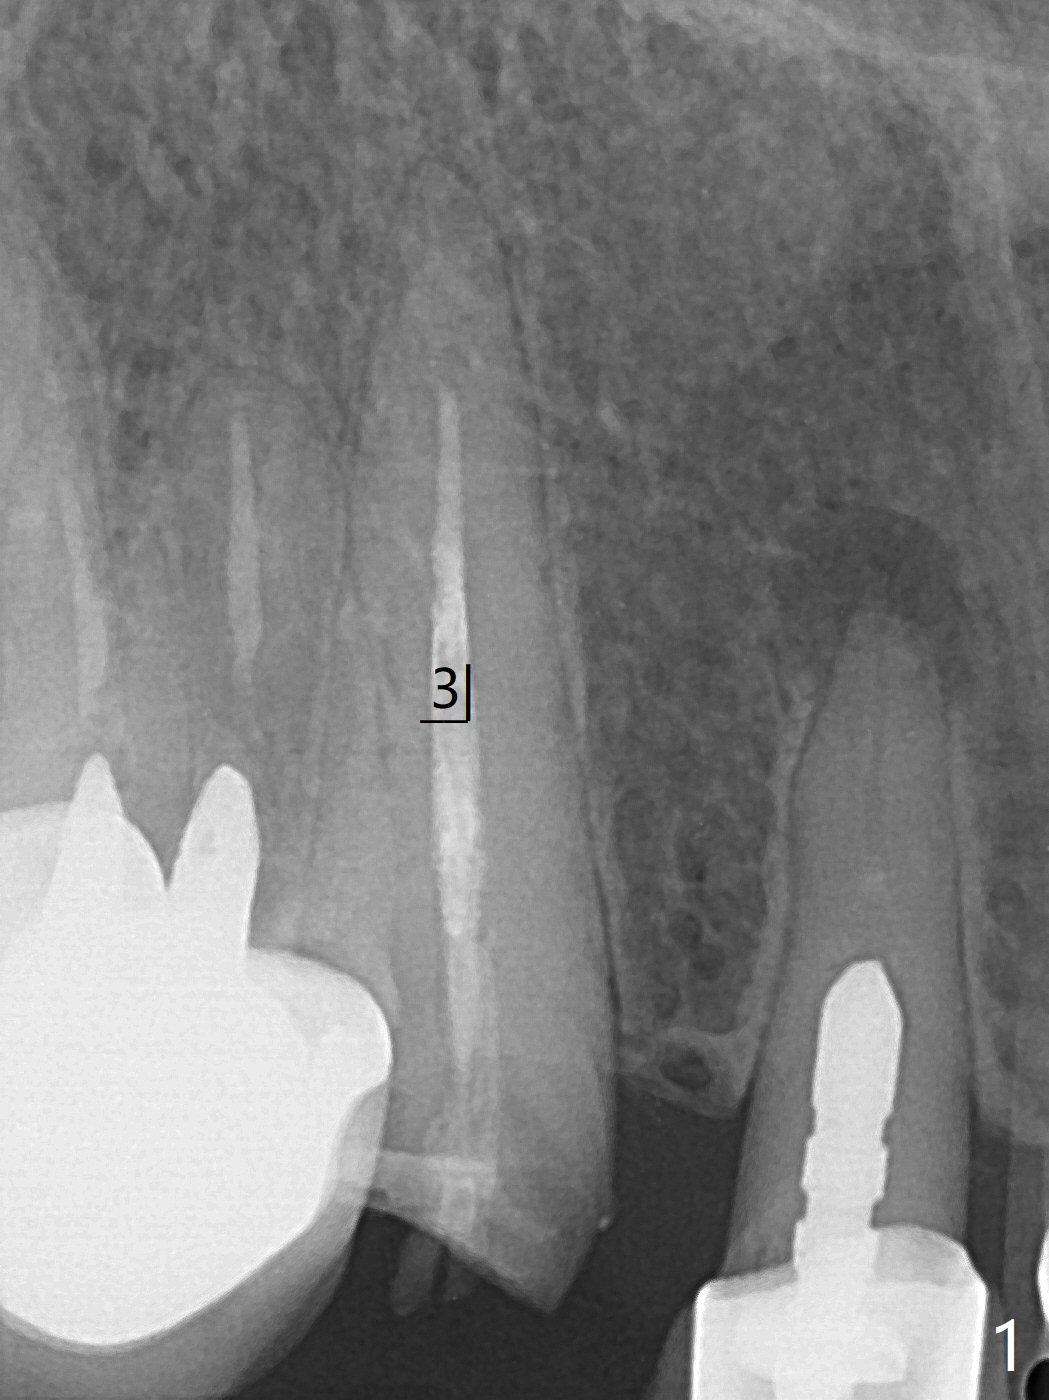

60岁女比较瘦小,8个月前因右下4,5轻度植体周围炎(4.5毫米软组织水平两段式植体种得太颊侧)就诊,准备重做,后来由于口腔卫生改善,症状减轻,她不愿意手术。右下6种植两个2.5x10毫米一段式种植。最近右上尖牙折裂,部分龈下(图一),她果断选择拔除种植。根尖片显示足够空间植入4.5x20毫米软组织水平植体(图二)。8个月前拍摄CT冠状面表明有充分根尖骨质(图三),植入3x14毫米骨水平一段式植体,便有2毫米颊侧,腭侧骨壁(减少植体周围炎可能性),而且修复角度优越(图四)。我可能在腭侧牙槽窝下1/3骨壁垂直钻入,然后改变钻洞方向,如红线,临床上,由咬合关系决定方位。如果不行,我有15度一段式植体。Bendable植体来不及买了。